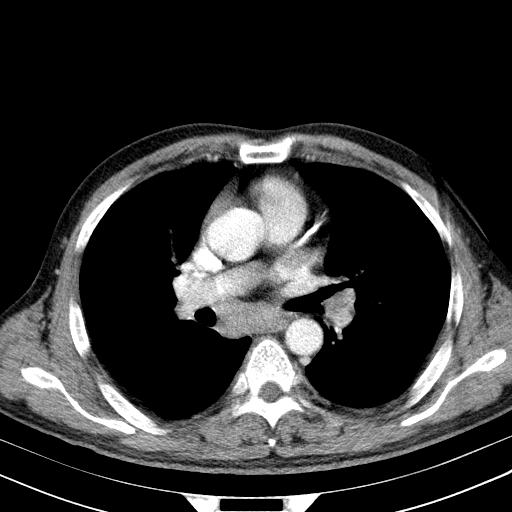

先行ct平扫,纵膈内多发软组织影,ct值约为36hu,以下为增强扫描和腹部平扫。

经典?纵膈多发肿大淋巴结。腹膜后未见异常。

大家看看肝脏右叶片状低密度影是什么改变啊?

淋巴瘤?肝脏请增强后说啊

多发肿大淋巴结影,肝内改变需结合强化观察